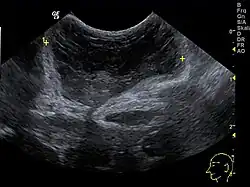

Die Ausstülpung mitsamt knöchernem Defekt kann sonographisch und durch Magnetresonanztomographie bereits pränatal nachgewiesen werden.[12][13]